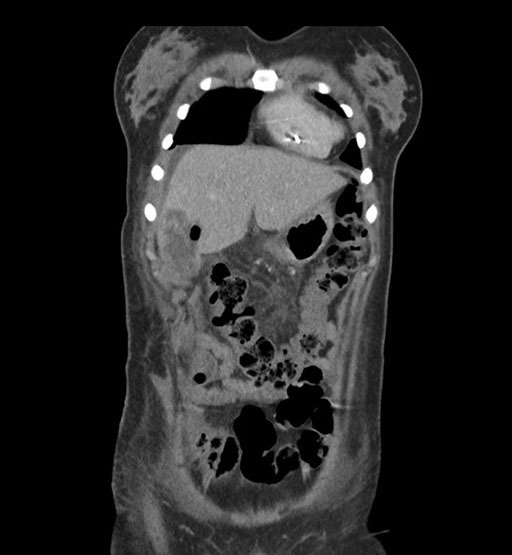

Coronal Arterial

Imaging analysis

Based on initial findings, which issue(s) would you be most concerned about?